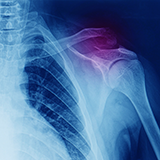

If you have suffered a shoulder injury, it is important to understand the common conditions associated with it. From fractures and dislocation to tendon injuries and arthritis, there are a variety of issues that may be affecting your mobility, range of motion, or general quality of life.

Are you experiencing pain in your upper extremities? Do minor movements cause discomfort, or does it become unbearable when trying to do everyday tasks? If so, you may be dealing with a shoulder injury. Upper extremity injuries can vary greatly, from shoulder dislocation and rotator cuff tears to nerve damage caused by trauma. Understanding the symptoms of common shoulder injuries is essential to diagnose and treat the issue appropriately.